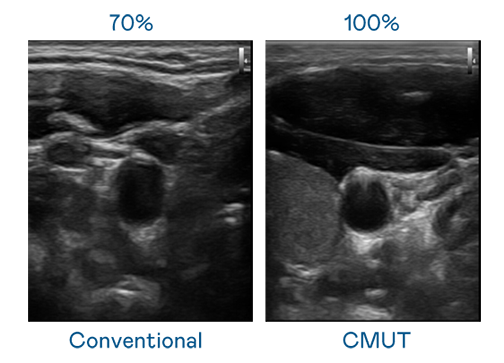

CMUT 技术是一种用电容式微机电元件来产生超音波讯号的技术。与传统 PZT 压电式技术相比,CMUT 频宽增加 30%,更宽频的超音波讯号让影像解析度大幅提升,是实现高影像品质医疗超音波扫描、促进精准医疗发展的关键技术。

超音波影像的解析度高低,首先取决于探头能发出的讯号频宽。DG视讯 CMUT 可提供高清晰的超音波讯号,提供高频宽、高灵敏度、影像纹理细节更高的超音波影像,协助医护人员缩短影像判读时间及利用精准的医疗影像进行诊断。